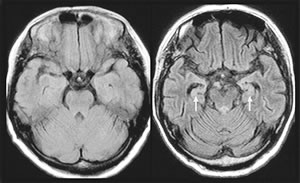

専門医療機関では、MRI(電磁波を使った断面撮影)をしてもらっています。左が正常な脳で、右がアルツハイマー型認知症です(写真)。アルツハイマー 型認知症では脳室(部屋のような部分)が大きくなります。海馬が萎縮するからです。

海馬は記憶をためる脳の組織です。従来は医師の主観で診断が左右されていましたが、いまは埼玉医科大学の松田博史教授により、海馬の萎縮を客観的に評価する解析ソフトも開発されています。

また、ごく初期のアルツハイマー型認知症では海馬の萎縮が起きていない例もあります。こういう方はSPECT(スペクト)といって、血流や脳の働きがよ い部分がわかる検査をします。アルツハイマー型認知症では、側頭葉(頭の側面)、頭頂葉(頭頂部)などの血流低下が起こります。こちらも解析ソフトが開発 されています。地域の基幹病院ではたいていこれらのソフトが導入されています。